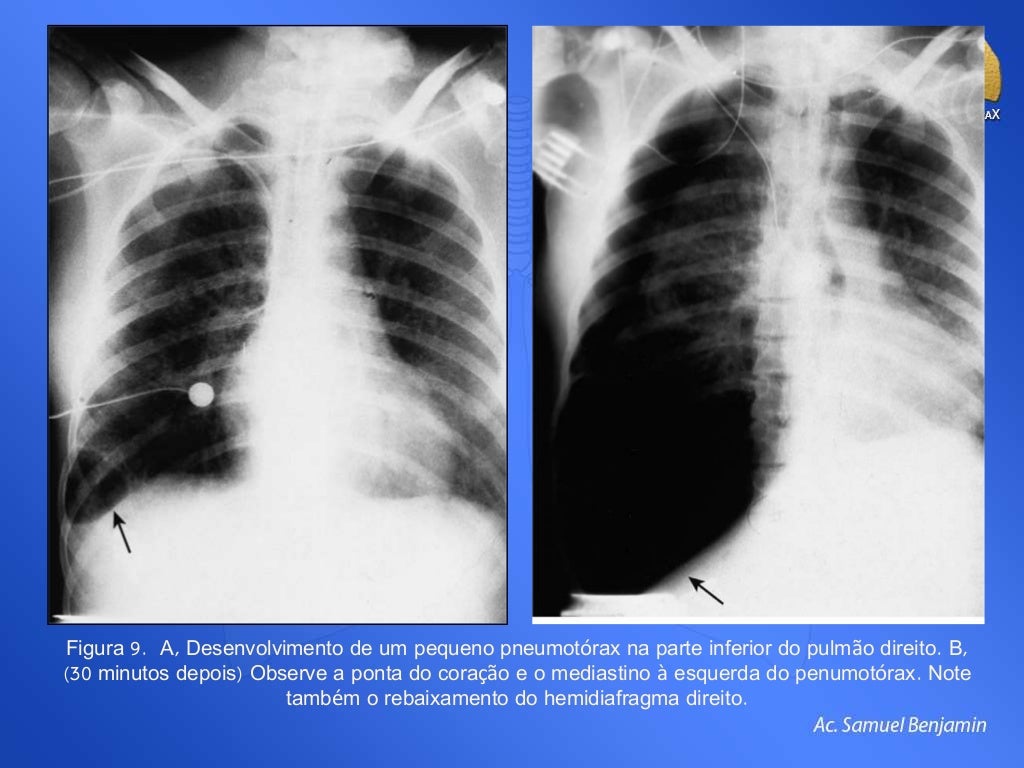

Pneumotórax. 1. hipertensivo: ocorre quando o orifício na pleura. 6. exerce um papel de válvula unidirecional, ou seja, cada vez que a pessoa inspira entra mais ar na cavidade pleural. 2. , o qual não consegue sair. É o tipo mais grave de pneumotórax. 1. e precisa ser reconhecido e tratado rapidamente, porque comprime e compromete.